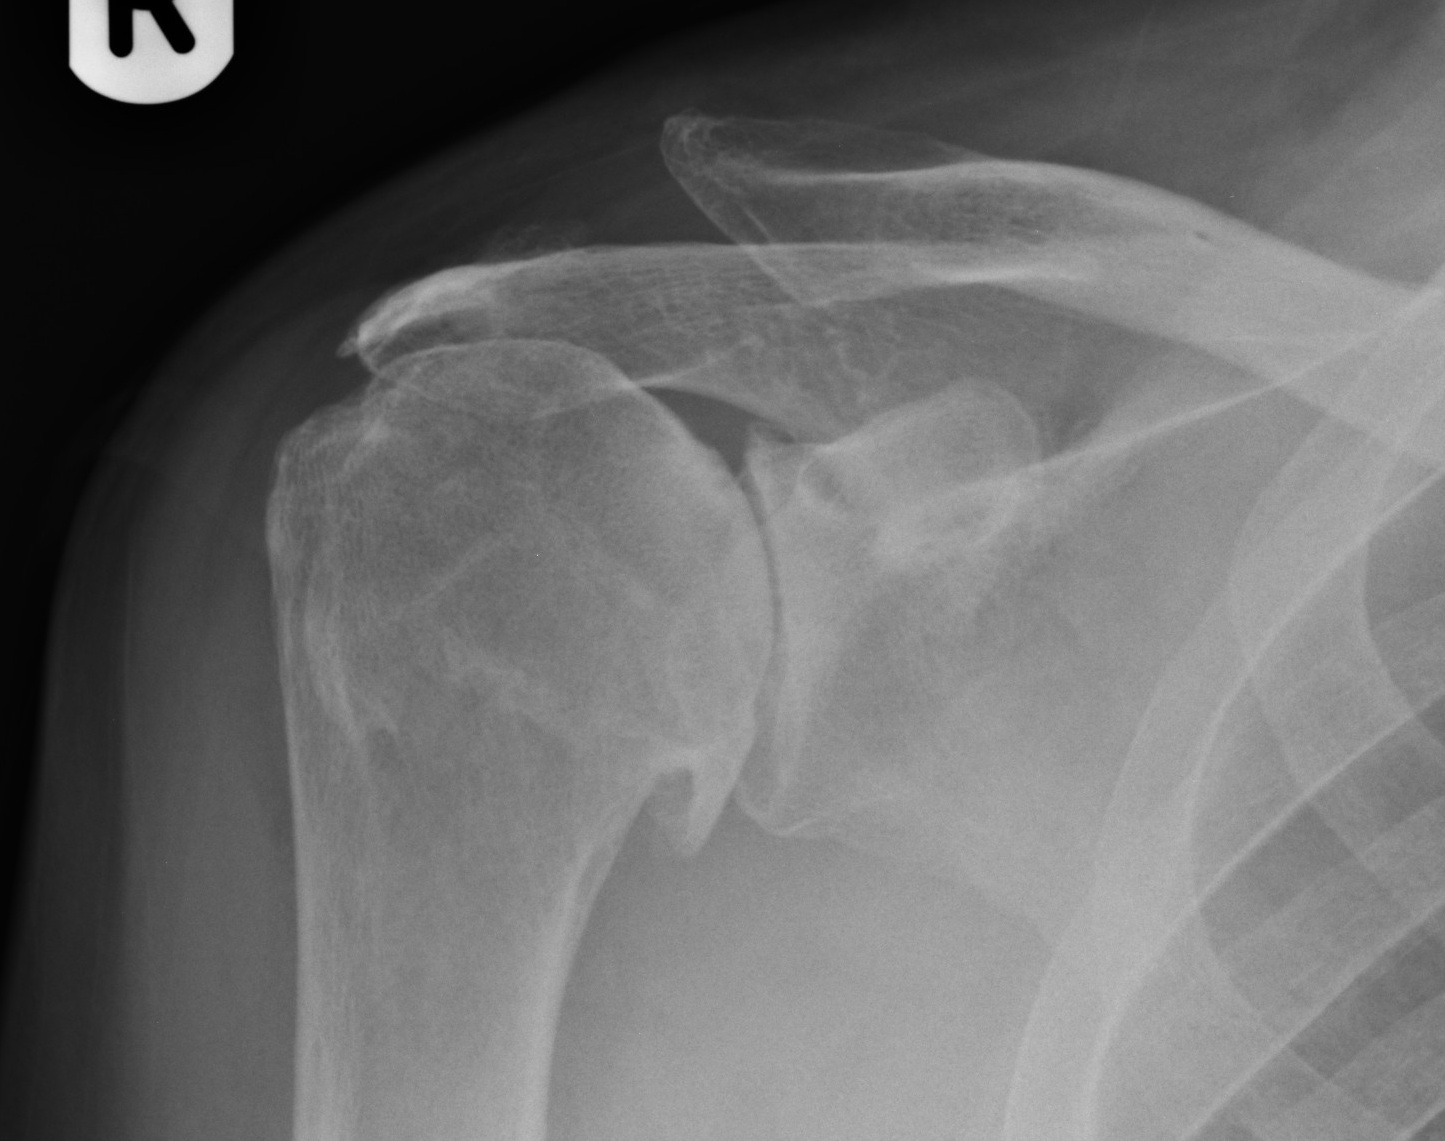

X rays and sometimes either an MRI scan or CT scan.

Operative: If there has been no improvement with physiotherapy then a shoulder replacement can be carried out. The exact type of replacement surgery depends on x-ray findings and the state of the rotator cuff tendon. In most situations, the ball and socket are replaced.